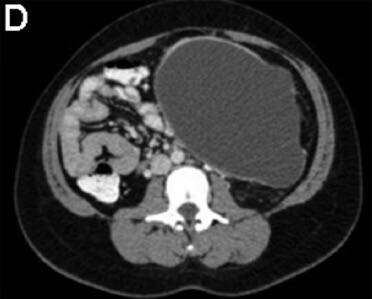

3个月前,她被电击中摔伤了腹部。当时这引起了上腹部疼痛;然而,她没有立即去医院直到3个月后才就诊。 该患者之前没有明显的病史或手术史,是一个非吸烟者,偶尔饮酒。 身体检查发现该女性健康,营养状况良好,唯一值得注意的是,腹部浅触诊时可于上腹部触及一个明显的肿块。 血常规检查包括全血细胞计数,尿素氮,电解质,葡萄糖,以及肝功能检查,均在正常范围内。血清淀粉酶66U/L,白蛋白43g/L,HIV 1/2 Ab/Ag酶联免疫吸附试验为阴性。 腹部对比增强计算机断层扫描显示连续轴向截面如图A-D。图E为矢状面。 剖腹手术时吸出低黏度,清澈,囊液,囊液生化分析显示,淀粉酶58903U/L,乳糖脱氢酶904U/L,蛋白质<10g/L。未获取囊性癌胚抗原和CA-19-9。在剖腹手术时对多个囊壁活检取样(图F)。

计算机断层扫描证实源自胰尾的一个大型,单房,囊性肿块,伴未分隔的附壁结节,或囊性钙化。影像学结果,临床病史,和囊液分析支持胰腺假性囊肿的诊断。出人意料的是,囊壁活检显示为良性粘液分泌柱状上皮,雌激素受体阳性,与良性粘液性囊壁肿瘤(MCN)一致。最终,执行远端胰腺切除术,并且此后恢复良好。鉴于MCNs已经确定的恶变可能(6%-27%的病例),这例患者“有惊无险”,按照计划因假囊肿接受胰囊肿胃吻合引流术可以避免恶性肿瘤转化的严重后果。